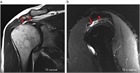

1. 肩関節の痛みの原因として、腱板断裂、石灰性腱炎、凍結肩(五十肩、肩関節周囲炎)、変形性関節症を想起すべきである(推奨度1)

1. 肩の痛みを訴える患者で、①棘上筋の筋力低下、②外旋筋の筋力低下、③インピンジメント徴候、の3つがそろっていれば98%の確率で腱板断裂と診断できる(推奨度2)